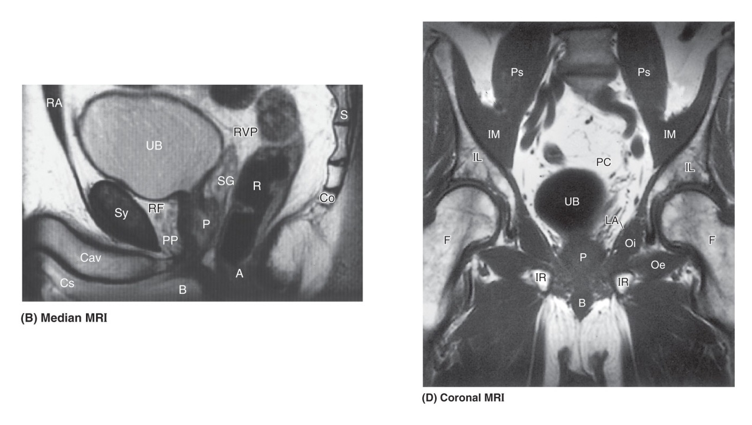

• The median view shows the relationship between the pubic symphysis (Sy), urinary bladder (UB), prostate gland (P), seminal vesicle (SG) and rectum (R).

The coronal image shows the bladder sitting immediately superior to the prostate gland. Immediately inferior to the prostate gland is the pelvic floor and then the bulb of the penis (B).

• The coronal MRI shows the highly coiled nature of the inside of the seminal vesicles (SG). At this coronal sectional level through the body, the structure posterior to the seminal vesicles can be seen appearing above and below the seminal vesicles – the rectum (R).

The transverse MRI image shows the crura (Cr) – erectile tissues that form the corpora cavernosa of the penis and the urethra (U) in the bulb of the penis. Posterior to this is the anal canal (A). Either side of the anal canal is a fat-filled space called the ischioanal fossa (IAF) part of the anal triangle.